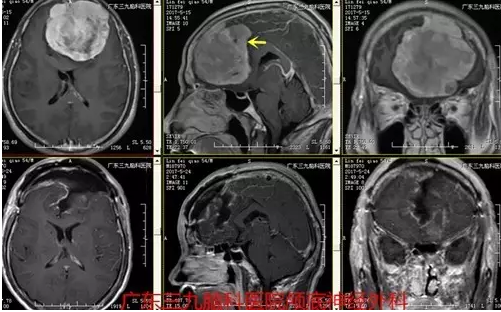

▲术后术后磁共振提示肿瘤全切

据主刀医生张良介绍,大脑镰旁脑膜瘤约占颅内脑膜瘤的总数的11%-13%,镰旁脑膜瘤居于大脑纵裂内,并从大脑半球内侧面突向脑内,并可沿大脑镰向前后侵犯,肿瘤位置较深,基底部较宽,上方有矢状窦和上引流静脉,下方有胼周、胼缘动脉和下矢状窦,手术空间狭窄,肿瘤显露困难,如处理不当,易出现对侧肢体偏瘫,术后癫痫等严重并发症,随着显微手术水平的提高,使得镰旁脑膜瘤全切率提高,手术并发症下降。上述患者林先生的病变亦位于前1/3,向对侧生长,病变大小约为7.5cm×7.2cm×7.5cm,体积较大,血供极其丰富,其内较多异常血管影,周缘较多血管缠绕,邻近双侧大脑前动脉受压移位,相对处理困难,术后MR见肿瘤全切,术后未见明确手术并发症。